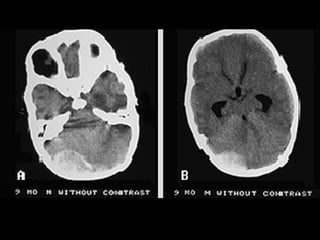

(1) TAC cerebral dilatación de las cavidades ventriculares secundarias

a un astrocitoma. (2)TAC cerebral: hemorragia en núcleos basales con

invasión ventricular